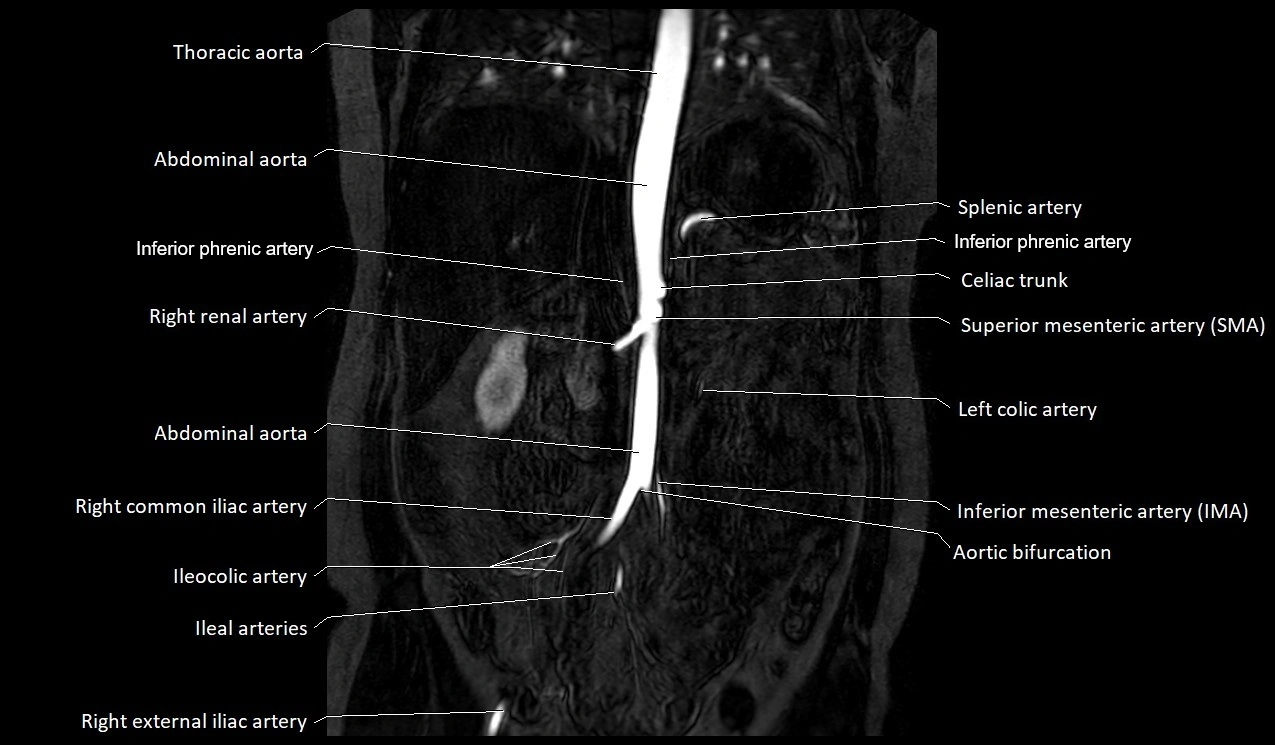

MRA Pelvis with Gadolinium:

-

Clearly delineates the origin, course, and anastomoses of the accessory obturator artery

Identifies connection with inferior epigastric artery, external iliac artery, or obturator artery

Excellent for detecting vascular variants prior to surgery

Useful in mapping pelvic vasculature in trauma, tumor embolization, or preoperative planning